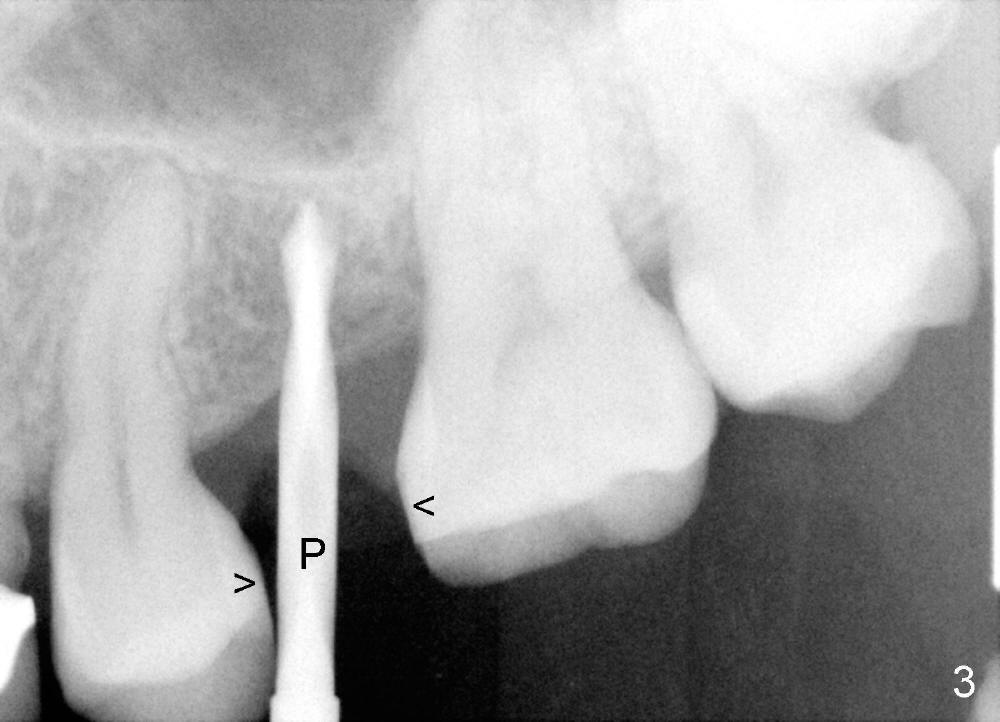

A 39-year-old lady is a dental phobic and finally agrees to restore long-termed missing upper left 2nd premolar (Fig.1). The adjoining teeth tilt toward the edentulous space. To place a 3.8x8 mm submerged implant (Fig.2, CBCT coronal section), enameloplasty is done (compare Fig.1 dashed lines with Fig.3 <). Since the density of the cancellous bone (<100 Hounsfield units (HU)) is much lower than that of the crest (300-400 HU) (Fig.2' <), osteotomy is initiated by 2 mm pilot drill (Fig.3 P) and finished by osteotomes (2 and 3 mm), bone expanders (2.6 mm (Fig.4) and 3.2 mm) and 3.8 mm tap drill. The implant is placed as planned with insertion torque around 35 Ncm (Fig.5). The implant is further lifted into the sinus by 1 mm without bone graft following the last X-ray. A healing abutment (4.1x3) is placed (Fig.6 <).